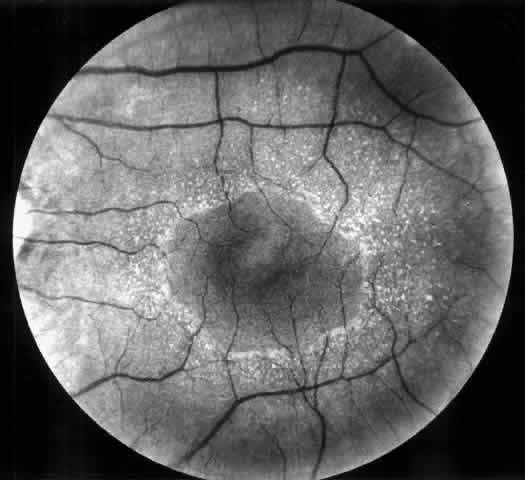

patients will probably never develop nephropathy.69,70 Retinopathy tends to deteriorate as renal failure develops, particularly

in patients with poorly controlled blood pressure and in patients in

whom no retinal treatment has been given before development of renal

failure. Hypertension changes the funduscopic aspect and the course of

background retinopathy by producing diffuse macular edema, cotton-wool

spots, and numerous flame-shaped hemorrhages, particularly in the peripapillary

area and along the main retinal veins (Fig. 5). In addition, hypertension accelerates the evolution of background to

proliferative retinopathy. Treatment of hypertension and of end-stage

renal failure will improve the retinopathy, particularly macular edema, and

stabilize vision.68 It is currently accepted that preservation of vision correlates well with

approach in preventing blindness.71  Fig. 5. Combined diabetic and hypertensive retinopathy in a 52-year-old patient

with long-standing diabetes and end-stage renal disease. Note optic disc

and retinal new vessels, diffuse retinal edema, numerous hemorrhages, and

several cotton-wool spots along the main veins. Fig. 5. Combined diabetic and hypertensive retinopathy in a 52-year-old patient

with long-standing diabetes and end-stage renal disease. Note optic disc

and retinal new vessels, diffuse retinal edema, numerous hemorrhages, and

several cotton-wool spots along the main veins.